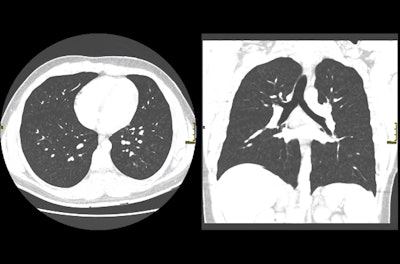

X-ray images showed diffuse micronodular opacities in both lungs and CT scans showed diffuse centrilobular nodules with a "tree-in-bud" pattern and subpleural spacing, signs consistent with bronchiolitis. His physicians later diagnosed him with acute bronchiolitis, which led to nearly fatal respiratory failure and chronic airflow obstruction.